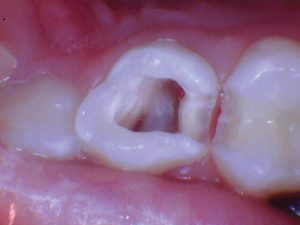

Figura 3. Después de quitar el techo de la cámara pulpar. |

Figura 4. Después de excavar el tejido pulpar en los orificios del canal, se utilizó una prenda de algodón seco para evaluar la salud de la pulpa mediante la aplicación de hemostasia por presión. |

Figura 5. Esta pulpa exhibió una pulpa radicular sana como lo demuestra el sangrado fácilmente controlado. |

Figura 6. Se colocó una capa de 2-3 mm de Biodentine seguida de una capa de Ionoseal (Voco) para evitar el lavado de ATM al proceder con el proceso de restauración. |